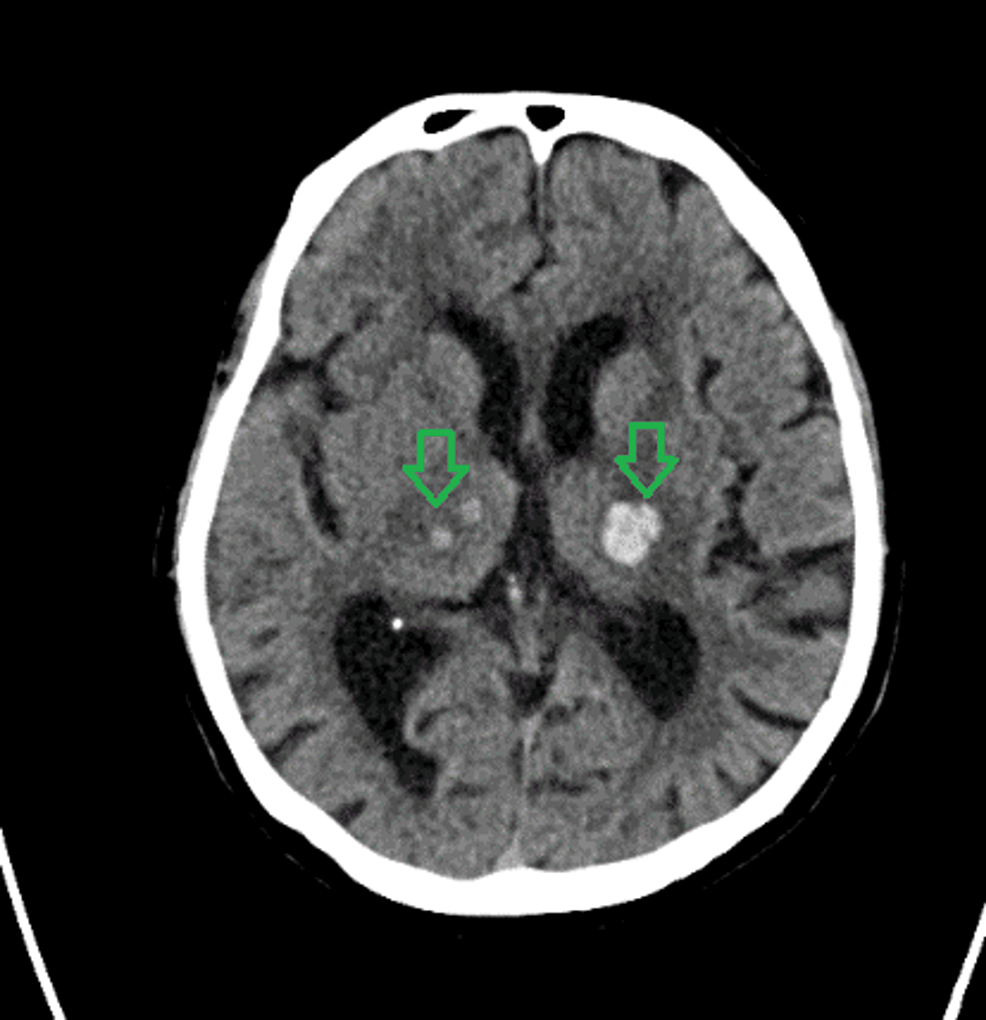

From www.researchgate.net

(a) Patient 1 initial plain CT showing bilateral basal ganglia bleed Basal Ganglia Bleed This article covers the latest research on blood pressure. The basal ganglia overall affects working memory and cognition, therefore limiting voluntary activity or motor movements. Hemorrhage in the basal ganglia causes contralateral hemiplegia and a gaze preference to the side of the bleeding owing to. When this is severely impacted the term “abulia” is used to describe the deficits. Learn. Basal Ganglia Bleed.

From www.semanticscholar.org

Simultaneous bilateral hypertensive basal ganglia hemorrhage Basal Ganglia Bleed Find out the diagnosis methods, treatment options and. This article covers the latest research on blood pressure. When the basal ganglia damage occurs, a decrease in “drive, initiation or motivation or emotional blunting” is often encountered. Hemorrhage in the basal ganglia causes contralateral hemiplegia and a gaze preference to the side of the bleeding owing to. Find out what causes. Basal Ganglia Bleed.